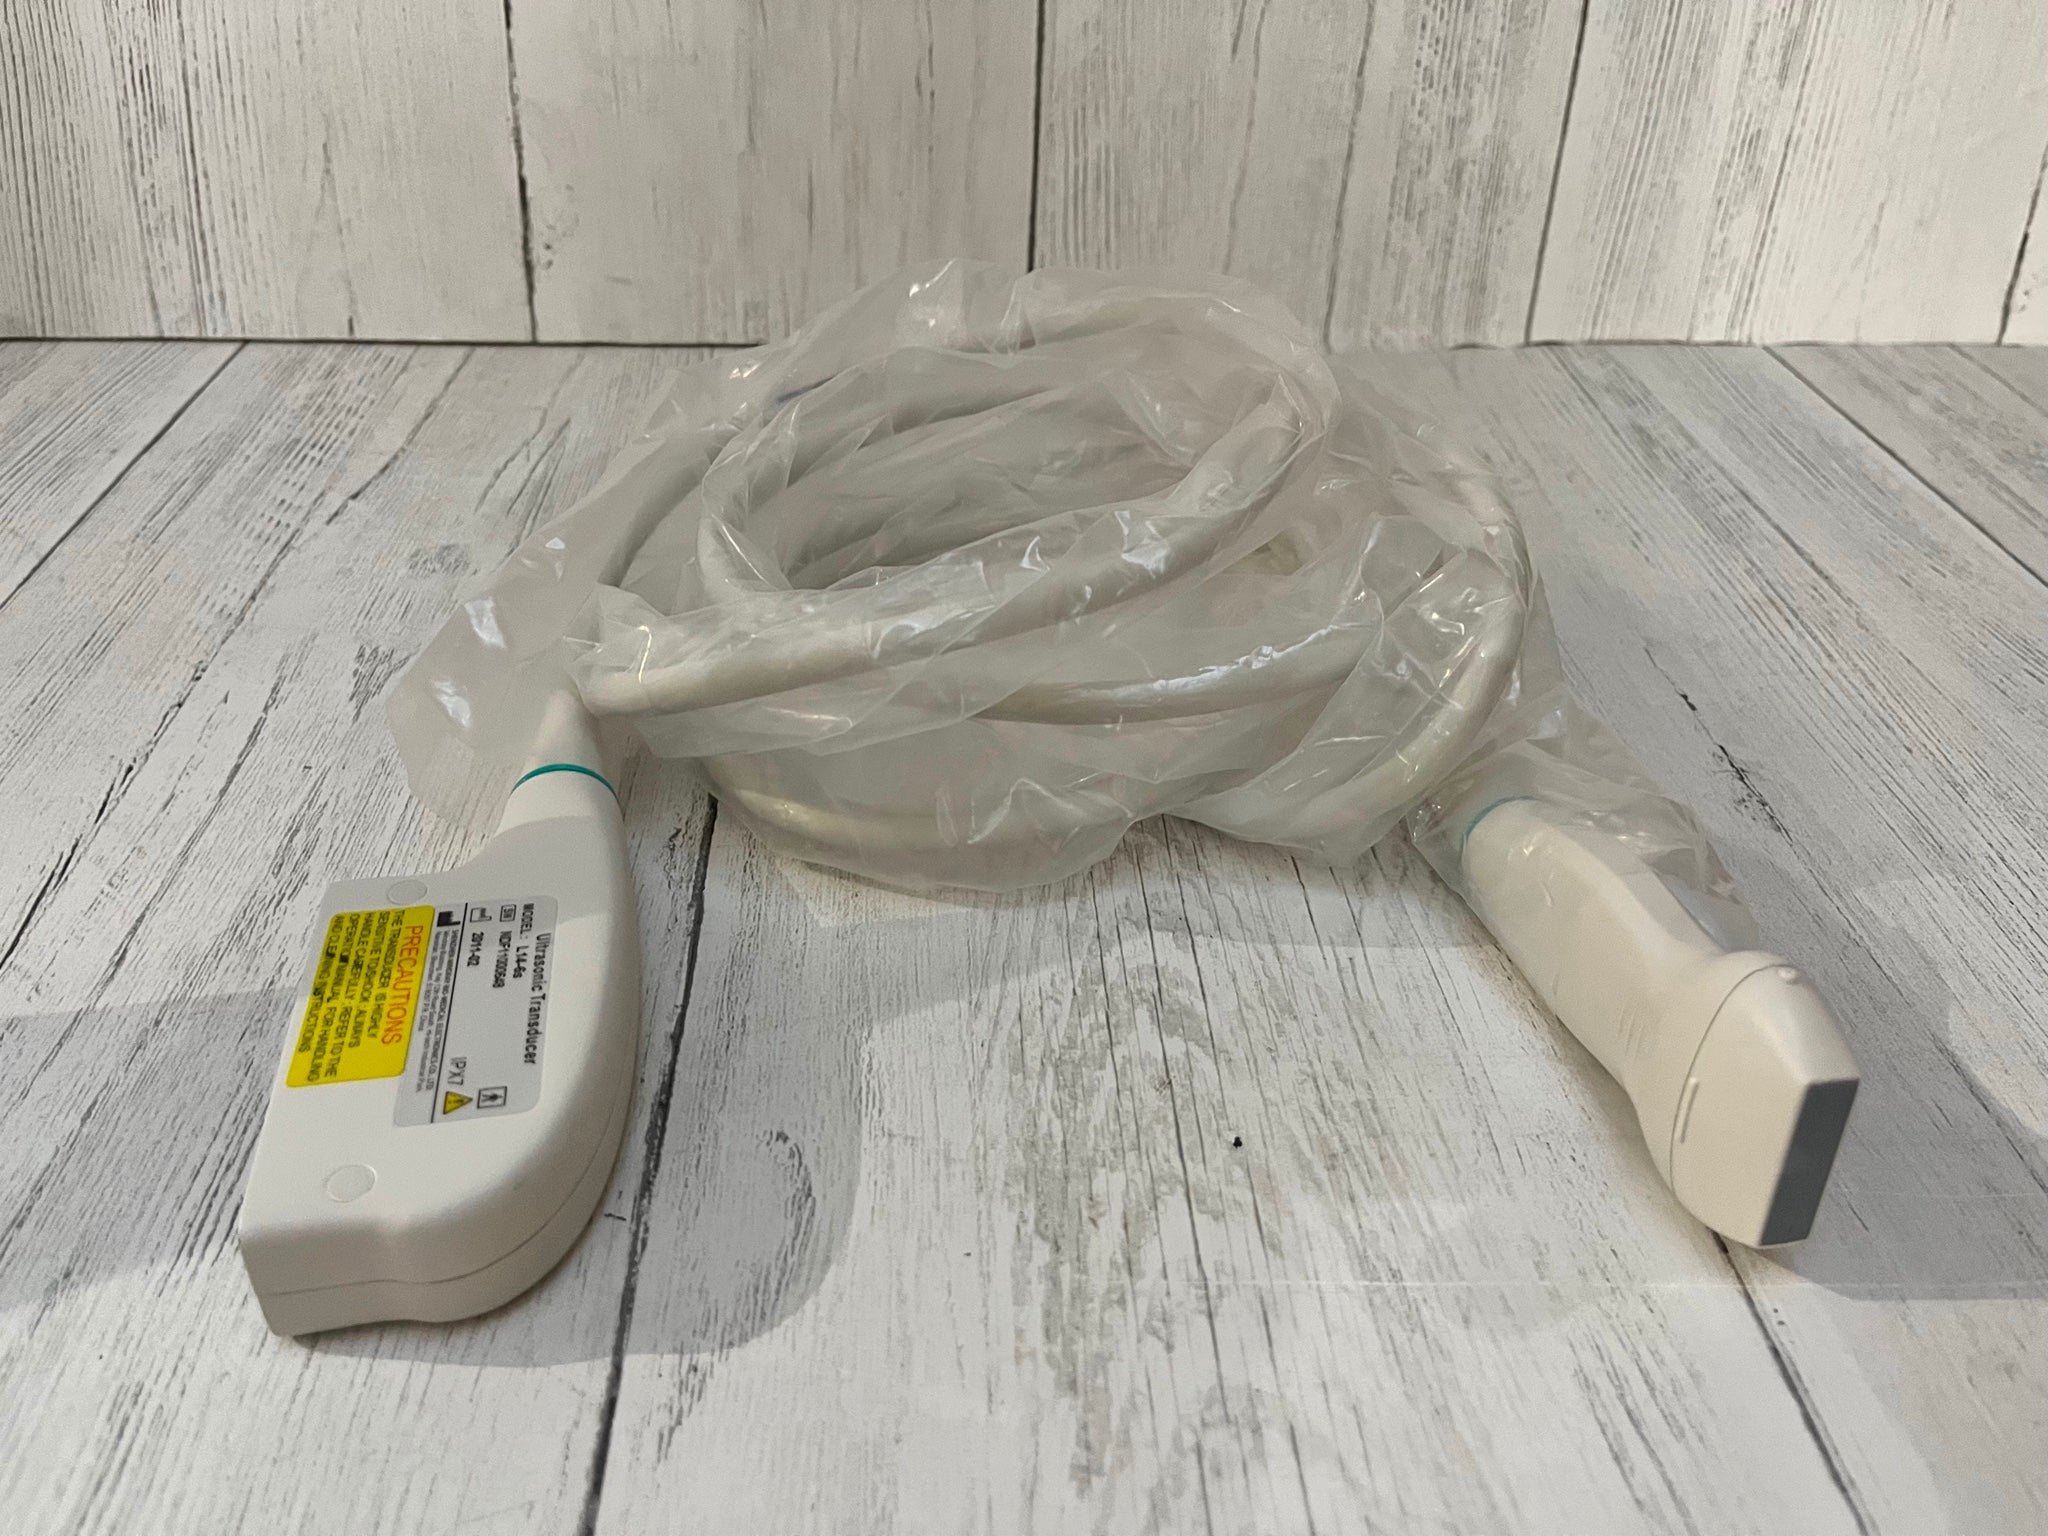

Seller Notes:âThe unit is in good cosmetic condition with some signs of wear and tear consistent with normal use (See Pictures). The unit was tested at our facility and found to be in good working order. Samsung Medison 3D 2-6ET 3D/4/D Convex Probe Bandwidth: 2 â 6 MHz Applications: Abdomen, Obstetrics, Obstetrics Early, Gynecology, Fetal Heart S/N: 275-K-A330Aâ